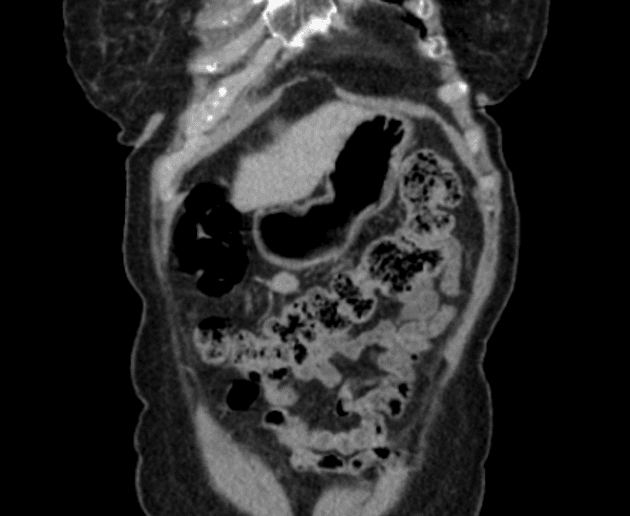

- Tổn thương dạng thùy (lobulated) kích thước 35 x 45 mm nằm ở phân đoạn V của thuỳ phải, liền kề với túi mật (gallbladder).

- Tổn thương này tăng tín hiệu (hyperintense) trên hình ảnh T2-weighted MRI.

- Trên hình ảnh cộng hưởng từ có tiêm thuốc tương phản động (dynamic contrast-enhanced imaging), thấy tăng quang dạng nốt (nodular) ở vùng ngoài viền (peripheral) ban đầu, tiếp theo là quá trình lấp đầy dần từ ngoài vào trong (slow centripetal filling).

Hình ảnh cộng hưởng từ (MRI) phù hợp điển hình với u sợi mạch gan (hepatic hemangioma).

U sợi mạch gan là khối u gan lành tính phổ biến nhất, thường được phát hiện tình cờ trên hình ảnh học. Bệnh xuất phát từ các mạch máu bất thường và gồm các khoang giãn chứa đầy máu được lót bởi tế bào nội mô. Trên cộng hưởng từ (MRI), hình ảnh điển hình bao gồm tăng tín hiệu rõ rệt trên T2 và kiểu tăng quang dạng nốt ở vùng ngoại vi trong thì động mạch, tiếp theo là quá trình lấp đầy dần từ ngoài vào trong ở các thì muộn. Dấu ấn hình ảnh này rất đặc hiệu, cho phép chẩn đoán chắc chắn không xâm lấn trong hầu hết các trường hợp. Mặc dù có thể sinh thiết, nhưng thủ thuật này tiềm ẩn nguy cơ chảy máu và thường được tránh. Điều trị mang tính bảo tồn, không cần cắt bỏ hay theo dõi định kỳ trong các trường hợp điển hình, trừ khi có nghi ngờ chẩn đoán hoặc bệnh nhân có triệu chứng.